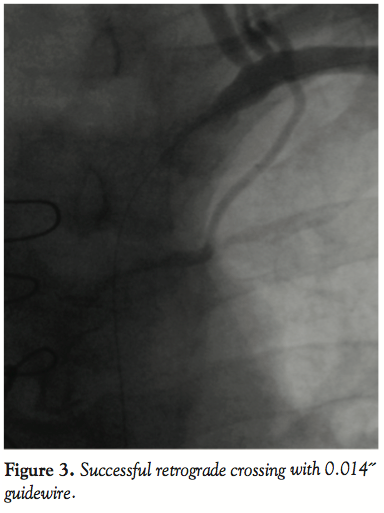

A 0.014˝ Choice PT graphix guidewire (Boston Scientific Corporation) was passed through the SC lesion via the transbrachial route with some difficulty. The guidewire was then advanced down into the iliac artery and pulled out of the femoral introducer using a GooseNeck snare (ev3, Inc., North Plymouth, Minnesota) (Figures 3 and 4). The wire was then introduced within a 5 Fr, 11 cm pediatric sheath (Cordis Corporation, Miami, Florida). A 5 Fr multipurpose guiding catheter (GC) was later advanced over the 0.014˝ wire and positioned just near the ostium of the left SC artery. The lesion was then predilated with a 2 x 20 mm and then a 3 x 20 mm Maverick balloon (Figure 5). Only then could the GC advance across the distal portion of the vessel to the lesion. At this moment, the 0.014˝ wire was removed and exchanged for a 0.035˝ wire (260 cm in length) through the GC. Then, the 5 Fr introducer femoral sheath was  exchanged for a 7 Fr, 61 cm SL2 sheath (St. Jude Medical, Daig Division, Minnetonka, Minnesota) positioned just near the ostium of the left subclavian and subsequently a 7 x 37 mm Express LD stent (Boston Scientific Corporation) was deployed in situ (Figure 6). Advancement of the GC across the lesion after predilation as well as all inflations within the SC artery were protected with prior LIMA 2.5 mm balloon inflation at 6 atm with subsequent deflation 5 seconds after deflating the subclavian balloon or stent. Post-dilatation of the stent was not performed. The LIMA balloon was withdrawn, then the Filterwire was retrieved with its  retrieval sheath (Boston Scientific Corporation) through the brachial sheath without any difficulty (Figure 7). The patient tolerated the procedure well and there were no complications. Some debris was retrieved in the Filterwire.